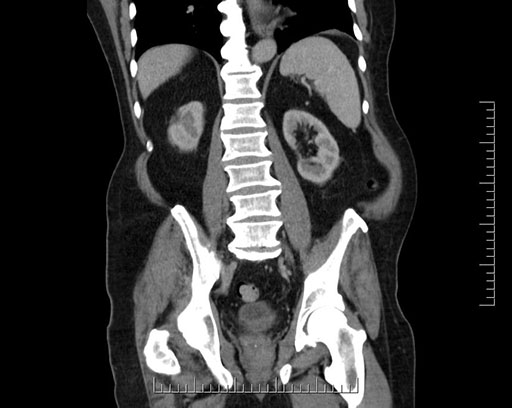

Coronal - stented